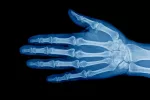

El tratamiento de la pubertad precoz dependerá de la causa que la haya provocado, y puede ser médico o quirúrgico (en el caso de quistes o tumores). En el 90% de los casos, al ser de origen central, tiene como objetivo suprimir esa anómala activación del eje hormonal hipófisis-hipotálamo-gónadas, para detener la secreción de hormonas sexuales, y frenar el desarrollo de los caracteres sexuales secundarios y detener la maduración ósea adelantada, evitando así el acelerón de crecimiento y conservando el potencial de talla adulta. Para ello se administra un tratamiento hormonal (análogos de la gonadotropina) en forma de inyecciones intramusculares cada 25-28 días.

Es necesario mantener el tratamiento hasta que se considere que la edad ósea, la edad cronológica, la madurez psicológica y el pronóstico de talla final son los apropiados para reinstaurar la pubertad.